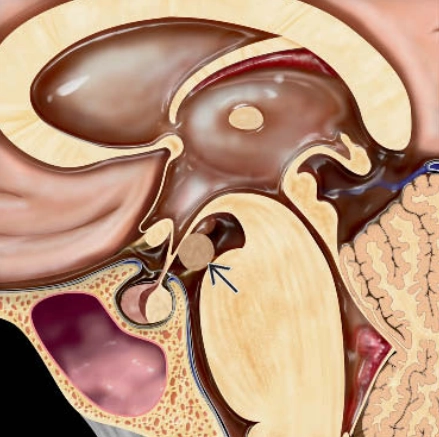

• Thoát vị móc hải mã (Uncal Herniation)- Thoát vị xuyên lều xuống dưới một bên (Unilateral Descending Transtentorial Herniation)

• Thoát vị trung tâm (Central Herniation)-Thoát vị xuyên lều xuống dưới hai bên (Bilateral Descending Transtentorial Herniation)